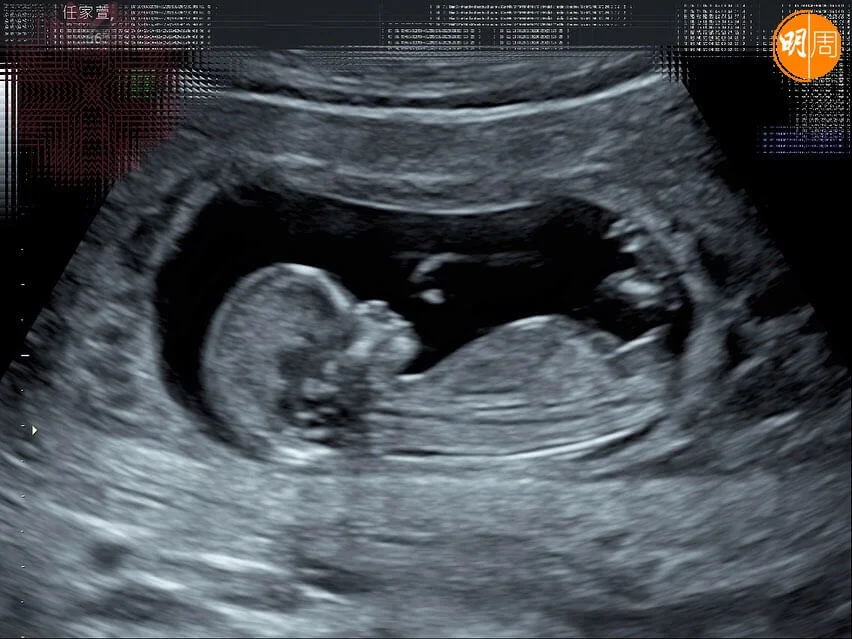

隨後Selina在社交平台貼上胎兒超聲波照,留言跟大家分享一個好消息,「我~懷~孕~了!」並透露她與兩位好姊妹陳嘉樺(Ella)和田馥甄(Hebe)對「小腰果」的稱呼感覺:「加滑(Ella)說:『好可愛的小名喔,喜歡」;甄說:『小腰果很中性,可男可女,可甜可鹹,可以帶皮也可以去皮,甚至頑皮』;我說:『腰果啊~彎彎的,似微笑的眼睛。上揚的,似笑開的嘴角!媽媽希望腰果是個快樂的小孩。』」並給小腰果送上打油詩:「女人四一一枝花,幸運生命正萌芽,彼此珍惜同步伐,大喜大樂請吃糖。春暖花開,我的腰果也來了」。她的喜訊獲圈中大批好友及網民留言祝賀。

據報Selina現已懷孕12周,在得知懷孕一刻第一時間爆喊,產檢聽到BB的心跳聲,她與小徐一同感動落淚。不過,Selina在懷孕2個月時,肚子已大到像6個月,原因是去年健康檢查時發現有4顆肌瘤,其中一顆大約4cm,幸好產檢後一切順利,肌瘤的位置不會影響到胎兒,只是肚子會比一般孕婦更大。Selina又謂沒想過自己41歲還能自然受孕,令她覺得很驕傲,也慶幸被BB選中她當媽。